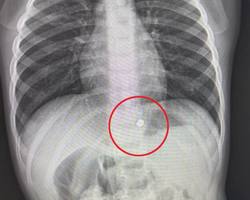

В Детский клинический центр имени Л. М. Рошаля поступил 2-летний мальчик с сильной болью в животе. Как выяснилось, ранее ребенок проглотил два магнита. Рентгеновские снимки подтвердили наличие этих магнитов в области желудка, что потребовало экстренной госпитализации и оперативного вмешательства.

— Мы провели мальчику гастроскопию в условиях операционной. В ходе процедуры мы обнаружили, что магниты сцепились друг с другом через слизистую оболочку, один из них находился в желудке, а другой в пищеводе. Из-за сильного магнитного поля магниты вдавились в слизистую, их было сложно захватить эндоскопическими инструментами. Поэтому мы использовали дистальный силиконовый колпачок, который позволил низвести магнит из пищевода в желудок, где магниты сцепились друг с другом и примагнитились к поднесенному эндоскопу, после были полностью извлечены из организма ребенка. Процедура заняла около 20 минут и прошла успешно, — сказал врач-эндоскопист Анастасия Лазарева.